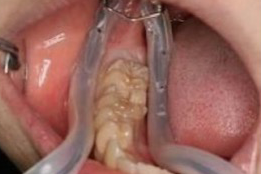

そこで私どもは、ラバーダム防湿という処置を行った上で根管治療を進めています。ラバーダム防湿は、治療する歯だけを隔離し、唾液や細菌の侵入を防ぐ装置です。ゴムのシートで患部以外を覆うことで、根管内を清潔で乾燥した状態に保ち、使用する薬剤が顔やお口の中に落ちないよう安全性を確保することができます。

この無菌状態での治療により、根管治療の成功率を高めることが可能です。根管の中に細菌を含んだ唾液が入るのを防げるため、再感染のリスクも大幅に減少します。

患者さまの大切な歯を守るために、こうした基本的な処置を丁寧に実施しています。